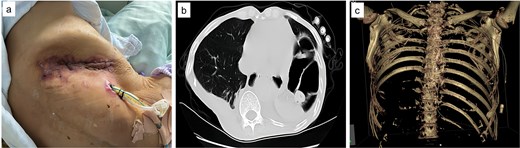

Upon admission, chest computed tomography (CT) and gastroscopy confirmed persistent esophagopleural fistula and empyema (Fig. 1a-c). A multidisciplinary team formulated a stepwise management plan: Stage 1: Under CT guidance, a chest drainage tube was reinserted. The nutrition team optimized nutritional status, correcting hypoalbuminemia and anemia. Thoracic drainage fluid culture revealed multidrug-resistant Pseudomonas aeruginosa; based on antimicrobial committee advice, local treatment (twice-daily 250-ml saline irrigation) was prioritized over systemic antibiotics. Stage 2: After 1 month, the drainage fluid became clearly transparent. However, CT showed unchanged fistula and cavity (Fig. 2a). Thus, a surgical plan was developed. CT-based three-dimensional reconstruction (Fig. 2b-d) guided surgery. Under general anesthesia, a 15-cm incision was made over the 10th rib. The latissimus dorsi muscle flap was dissected with preserved blood supply (Fig. 3a). Intercostal structures were preserved. The 9th and 10th ribs were transected 2 cm from the purulent cavity margin; the 11th and 12th ribs, 2 cm from the vertebral column. After thorough irrigation, a washable drainage tube was placed with its distal end toward the fistula. Muscle flaps were inserted into the cavity and sutured with antibacterial Vicryl (Fig. 3b and c). Finally, the incision was sutured (Fig. 3d). Stage 3: Skin depressions were compressed with cotton pads and a chest strap for 2 weeks (Fig. 4a). Sensitive antibiotics were administered for 2 weeks; intermittent saline irrigation-maintained drainage patency. The drain was removed at 3 weeks. Postoperative CT showed satisfactory recovery (Fig. 4b and c); the duodenal tube was removed 1 month later, and the patient resumed a normal diet gradually. As of July 2025, he remained symptom-free with no recurrence.

Intraoperative images. (a) Latissimus dorsi muscle flap with preserved blood supply; (b) rib transection and drainage tube placement; (c) muscle flap sutured into the cavity; (d) incision closure.